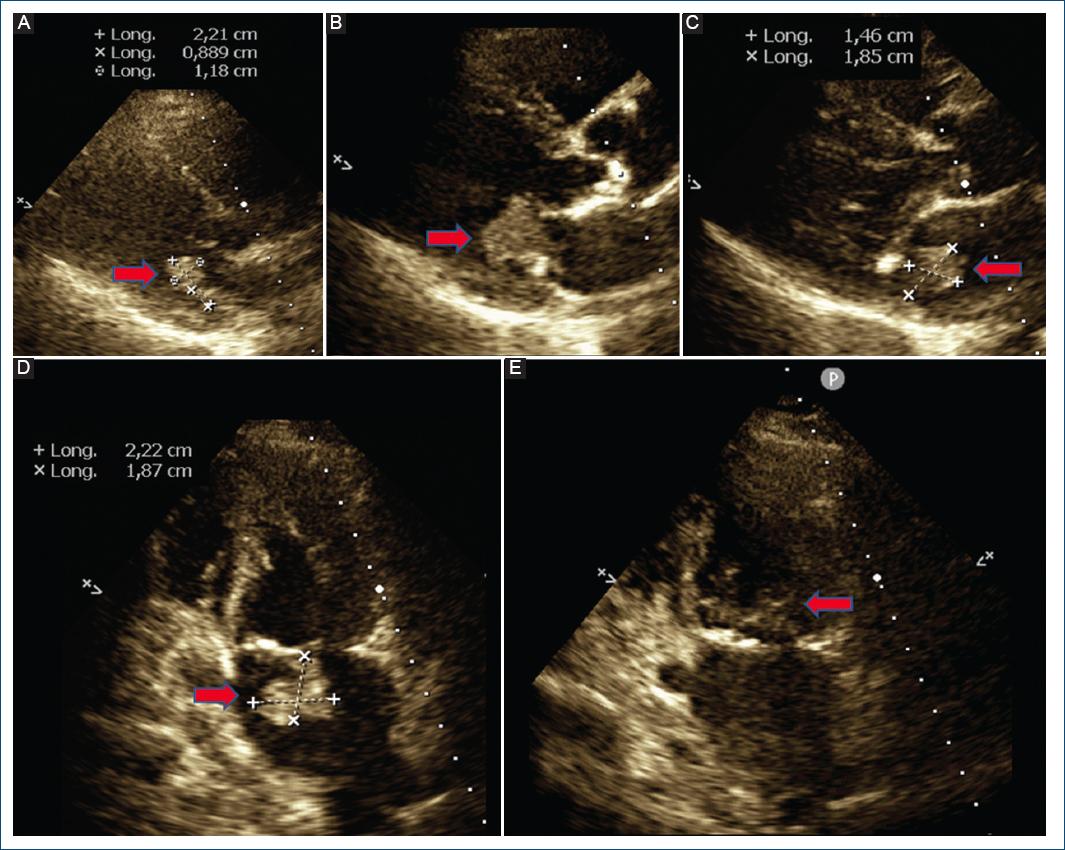

Fue derivada desde su ciudad de residencia por diagnóstico de posible endocarditis mitral, presentando pérdida de peso y sudoración nocturna de cuatro meses de evolución, descripción de una vegetación en valva posterior mitral y seis hemocultivos negativos. En nuestra institución se realizó ecocardiograma transtorácico, que evidenció masa móvil homogénea de 22 x 18 mm adherida a la valva mitral posterior de posible origen tumoral con protrusión hacia ventrículo izquierdo y generando insuficiencia mitral moderada (Fig. 1). No presentaba alteraciones en el electrocardiograma o el laboratorio. Se efectuó resonancia magnética (RM) cardiaca que informó la presencia de una masa en anillo mitral posterior de 20 mm hipervascular con captación y retención de contraste, y otra lesión similar pequeña en válvula aórtica (Fig. 2). Ante la sospecha de metástasis cardiaca, se realizó tomografía computarizada (TC) de abdomen y pelvis que detectó una masa isodensa heterogénea de 32 x 30 mm en el polo renal inferior derecho con necrosis interna y captación de contraste periférico, y un nódulo heterogéneo hipercaptante de 20 x 18 mm en glándula suprarrenal izquierda, ambos de origen neoformativo (Fig. 3). Se realizó TC de tórax que evidenció una masa hipercaptante subpleural a nivel basal posterior izquierdo de 29 x 28 mm que infiltraba los tejidos blandos y músculos intercostales adyacentes, además de múltiples nódulos pulmonares de hasta 5 mm compatibles con secundarismo (Fig. 3). La TC de encéfalo resultó normal. Se realizó RM de abdomen con contraste que detalló que la masa renal era compatible con neoplasia primaria y que el nódulo suprarrenal era compatible con secundarismo (Fig. 3). Se realizó biopsia renal, de una lesión pulmonar y de las subpleurales, compatibles con un carcinoma renal papilar de células claras con inmunohistoquímica positiva para vimentina y citoqueratina 7 en forma difusa y con patrón cup-like con anhidrasa carbónica IX. Se interpretó como carcinoma renal avanzado, con metástasis cardiacas mitral y aórtica (sin invasión de la vena cava), pulmonares, subpleurales y suprarrenal contralateral.

Figura 1 Masa adherida a valva posterior mitral evaluada mediante ecocardiograma transtorácico (flechas rojas). Vista paraesternal izquierda en diástole (A y B) y en sístole (C). Vista apical cuatro cámaras en sístole (D) y diástole (E).